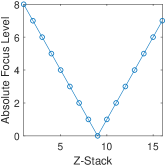

To generate a “subjective-like” score for FocusPath database, we assigned a “focus level” for each image that is determined by the difference between the best camera position and the position of interest . In other words, the score represents how far the camera is away from its best focus level when scanning a certain image slide. Specifically, every 16 images of the same content but different blur levels have a common and every image has a corresponding . A sample set of 16 images is shown in Figure 5. The value among every 16 images is determined by the proposed non-reference sharpness assessment metric in this paper. Since is found among 16 different slices of the same tissue content, the scores will guarantee to obtain the best focus level. The plot of focus level scores across 16 images is shown in Figure 6. The mathematical representation of the focus level for sharpness scoring is defined by